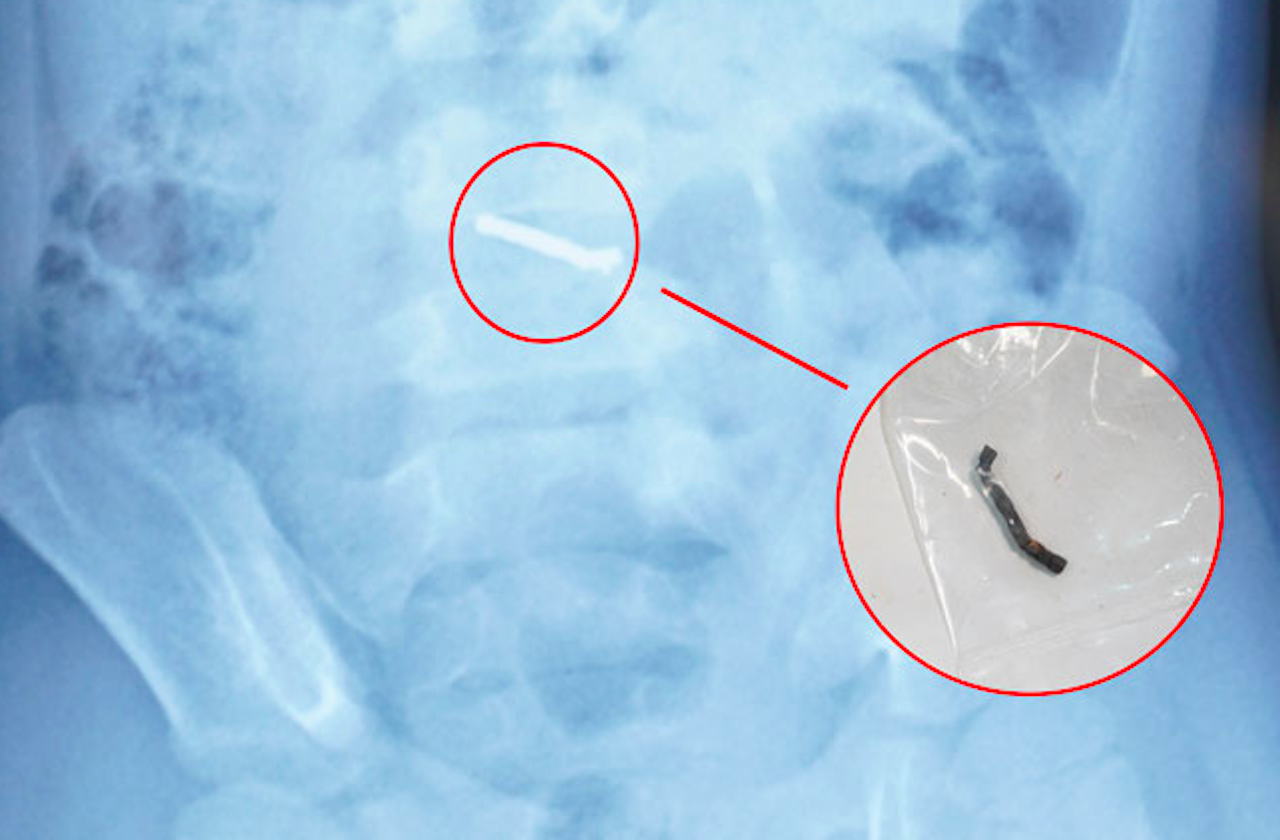

Trong quá trình phẫu thuật, các bác sĩ phát hiện nhiều viên nam châm nhỏ dính vào nhau thành một chuỗi, gây thủng ruột. Các bác sĩ phẫu thuật đã tiến hành lấy dị vật, khâu lỗ thủng và đặt dẫn lưu. Sau 4 ngày, bệnh nhi đã sinh hoạt bình thường, bắt đầu được tập ăn trở lại và dự kiến sẽ được ra viện trong một vài ngày tới.

Từ thông tin gia đình cung cấp về loại đồ chơi có các viên nam châm nhỏ có thể hút vào nhau, các bác sĩ chẩn đoán trẻ đã nuốt phải nhiều viên nam châm trong nhiều thời điểm. Sau khi xác định dị vật có từ tính và không thể tự đào thải ra ngoài, các bác sĩ đã tiến hành phẫu thuật cho trẻ.